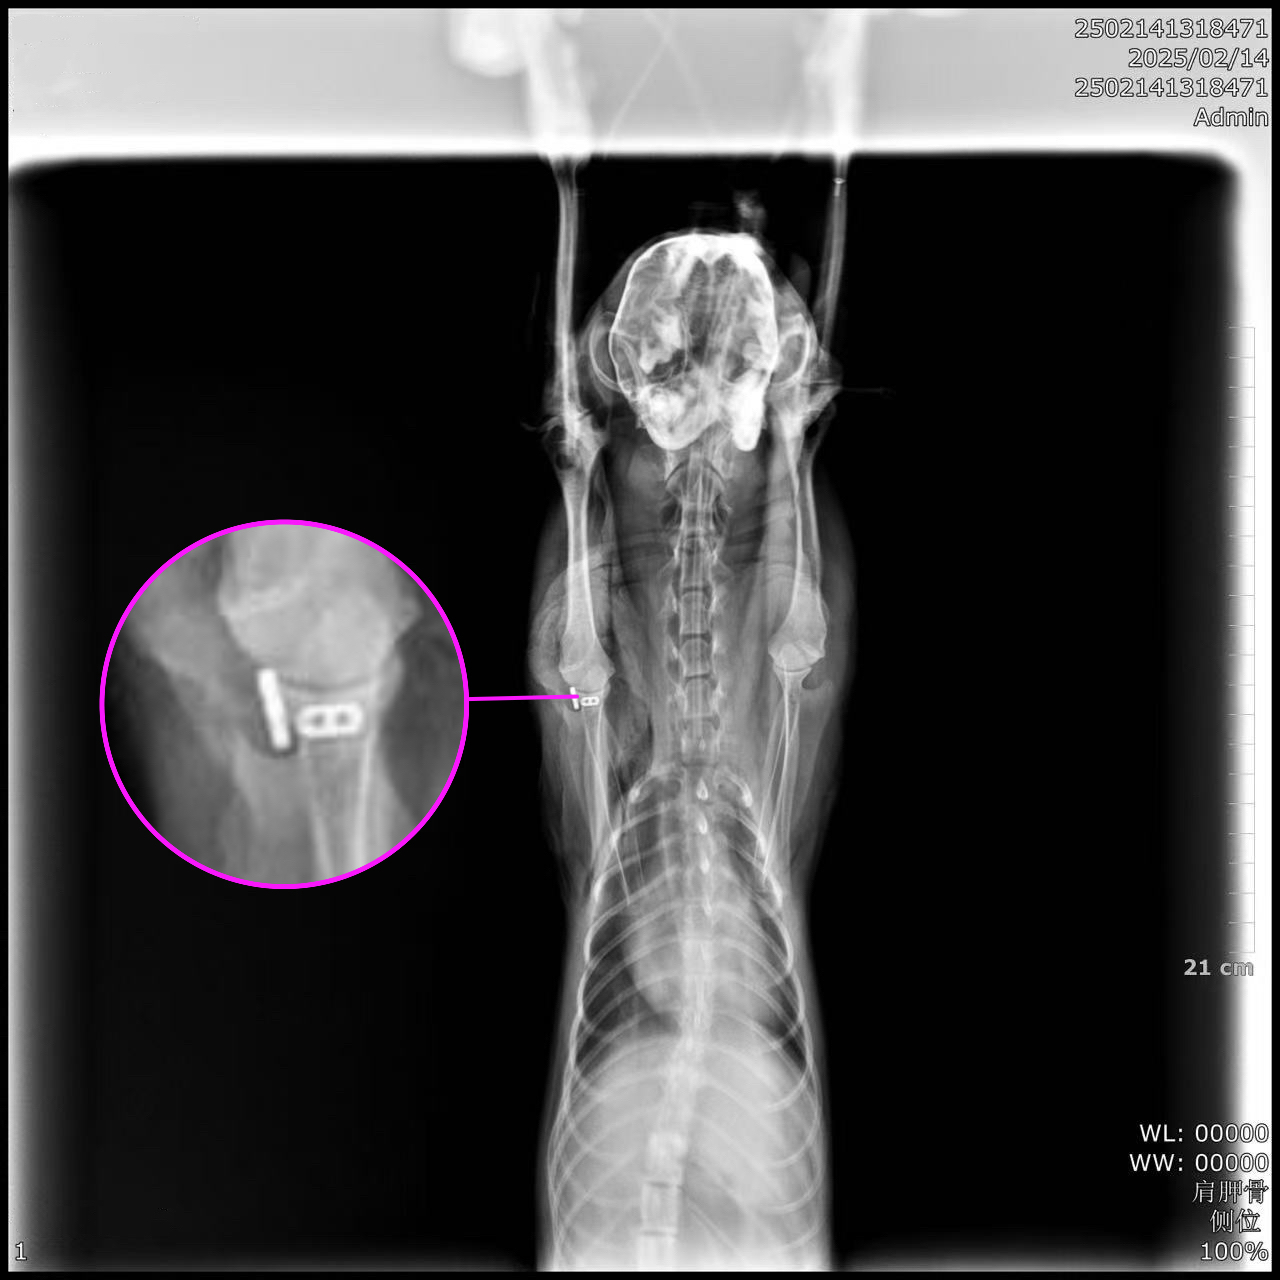

▼ Imaging

▼ Post-op Imaging